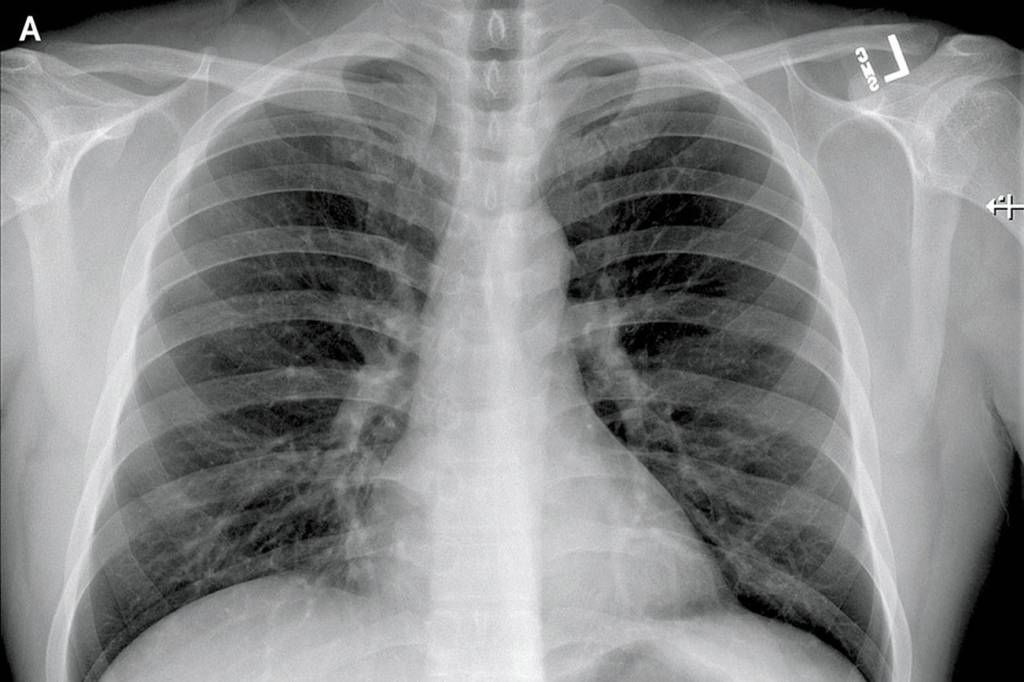

The article details the patient’s symptoms — everything from fatigue, nausea, diarrhea to a runny nose — over time and graphs his lab results. It shows X-rays of his lungs.